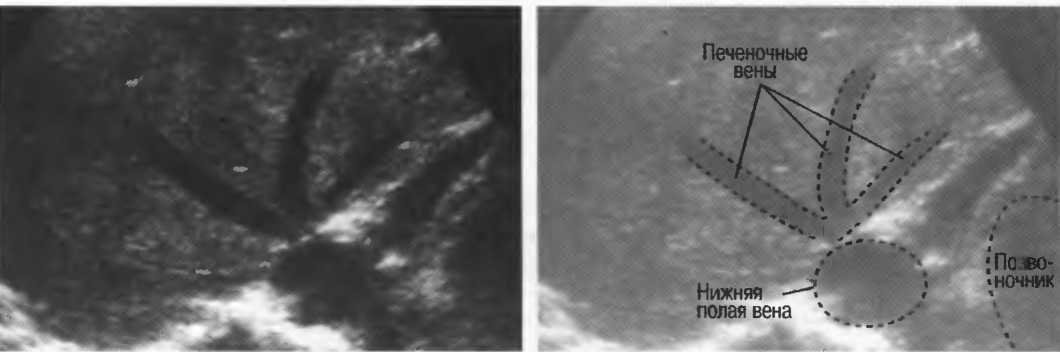

- Печеночные вены диаметром всего 3 мм должны визуализироваться при сканировании под углом 45° к поверхности нормальной печени (рис. 25).

Рис.25. Аппарат хорошего качества должен позволять визуализировать печеночные вены диаметром 3 мм. Этот тест может регулярно использоваться для контроля качества изображения.